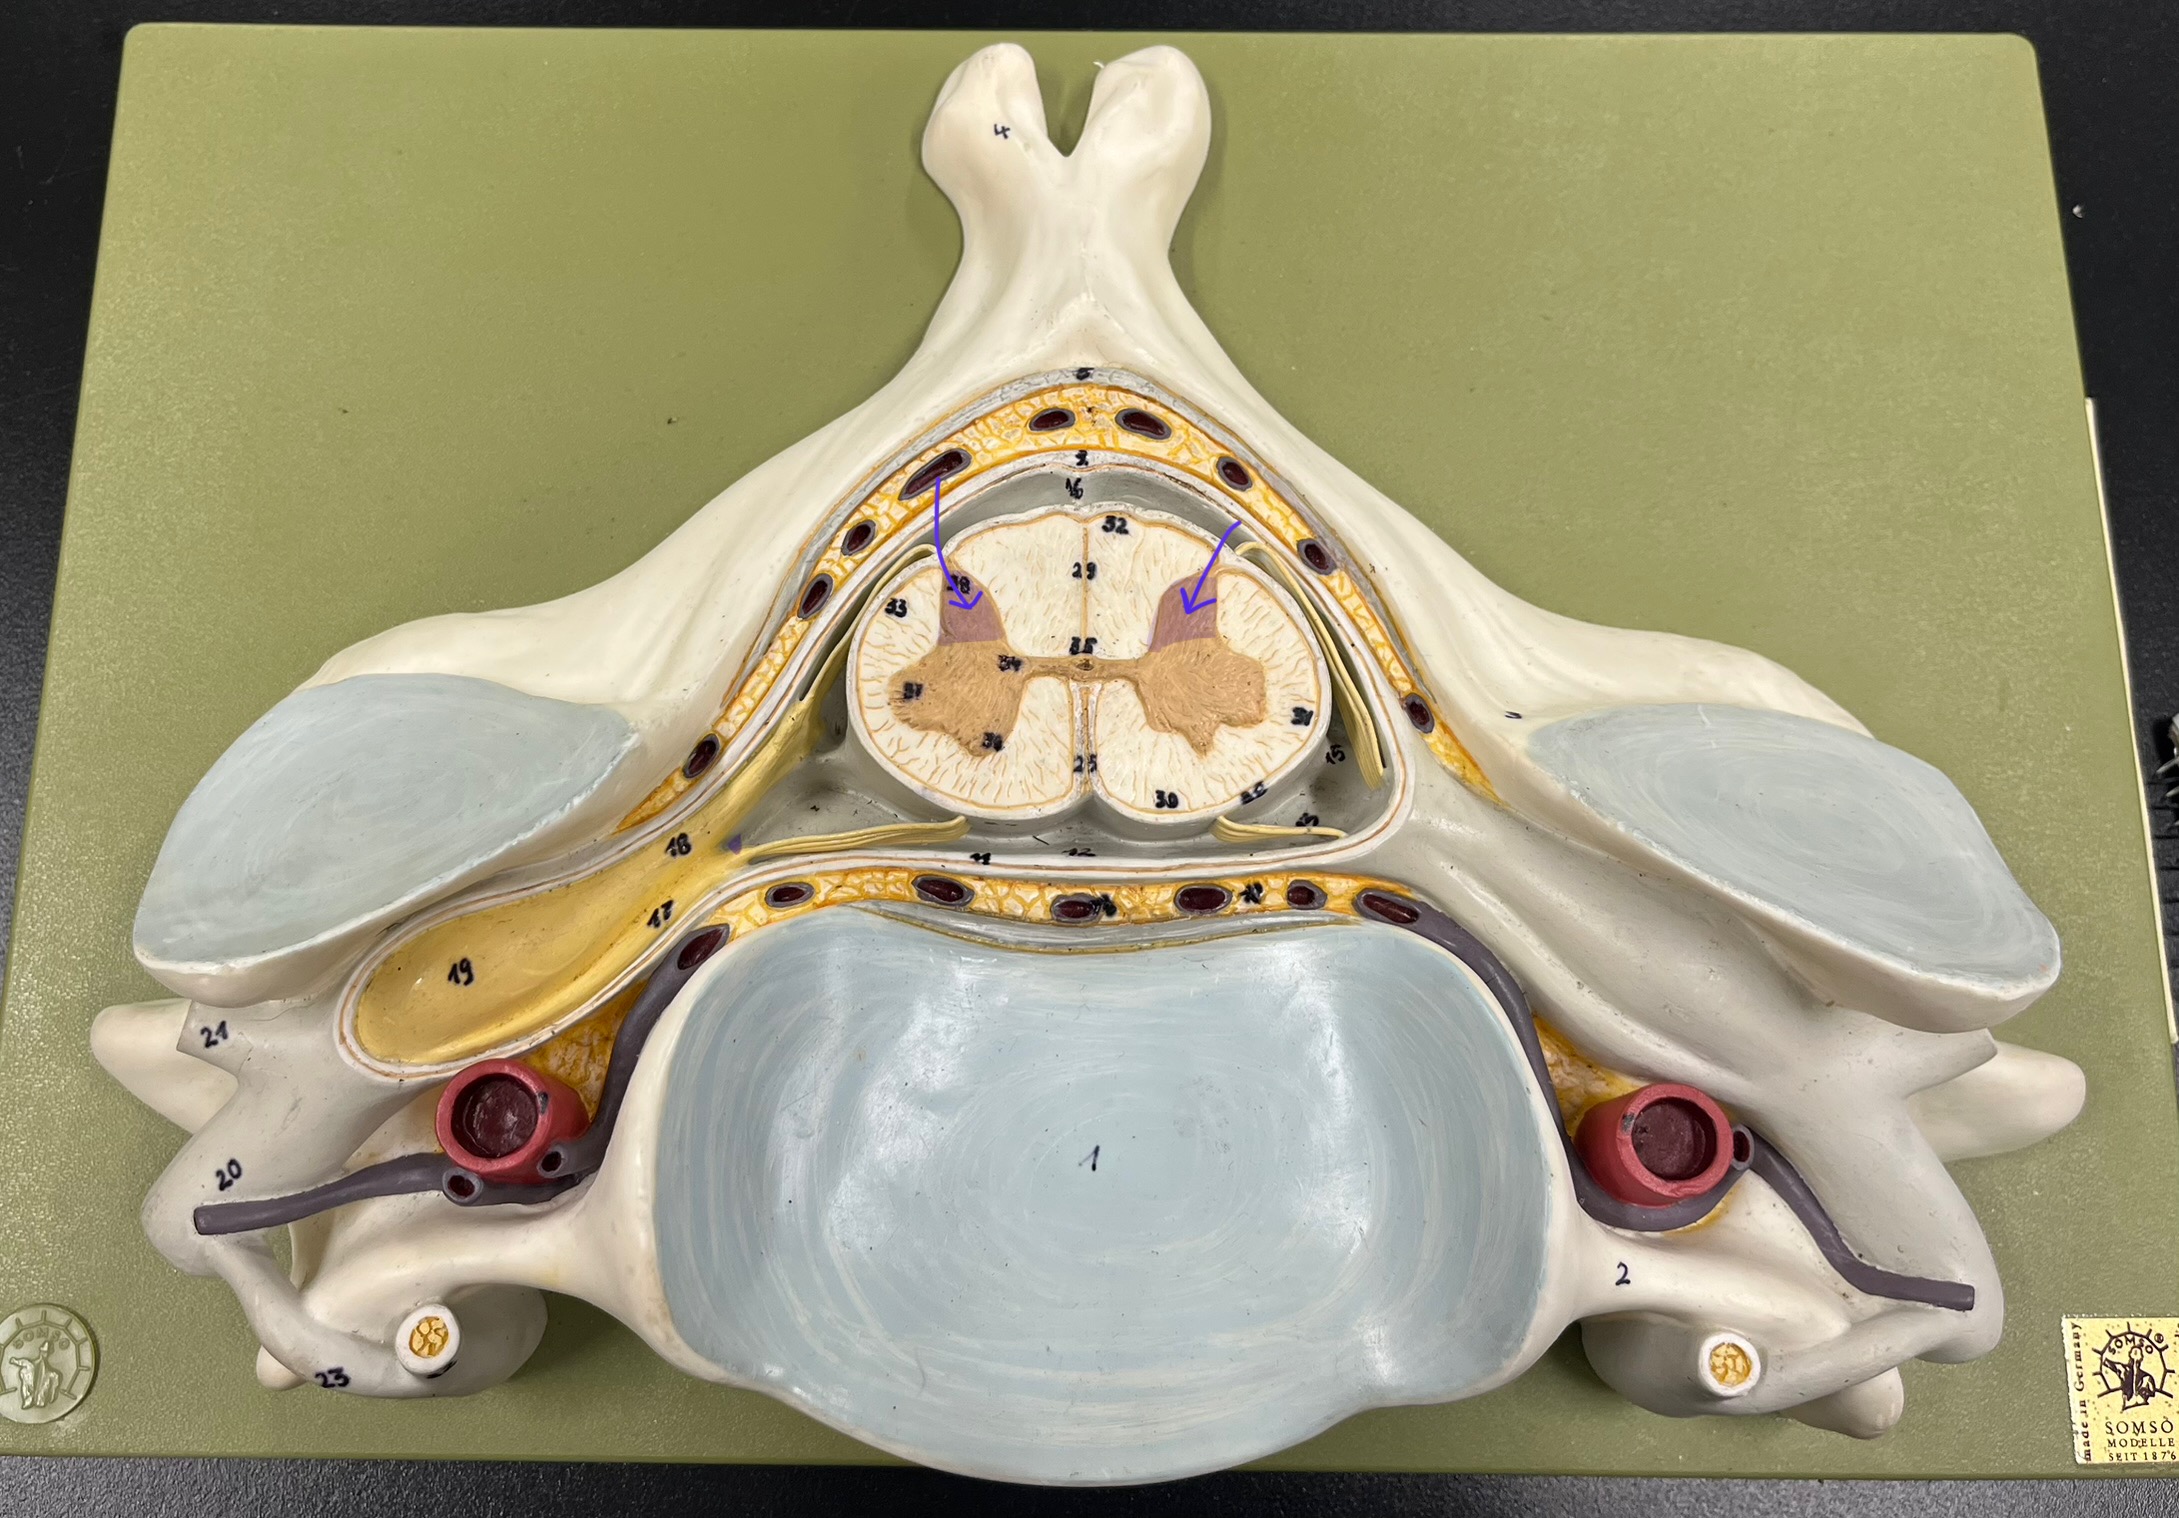

posterior (dorsal) horn

posterior (dorsal) horn; R—>L

anterior (ventral) horn

posterior (dorsal) root ganglion

What is the bulb here?

posterior (dorsal) root ganglion

posterior (dorsal) root

posterior (dorsal) root

anterior (ventral) root

anterior (ventral) root